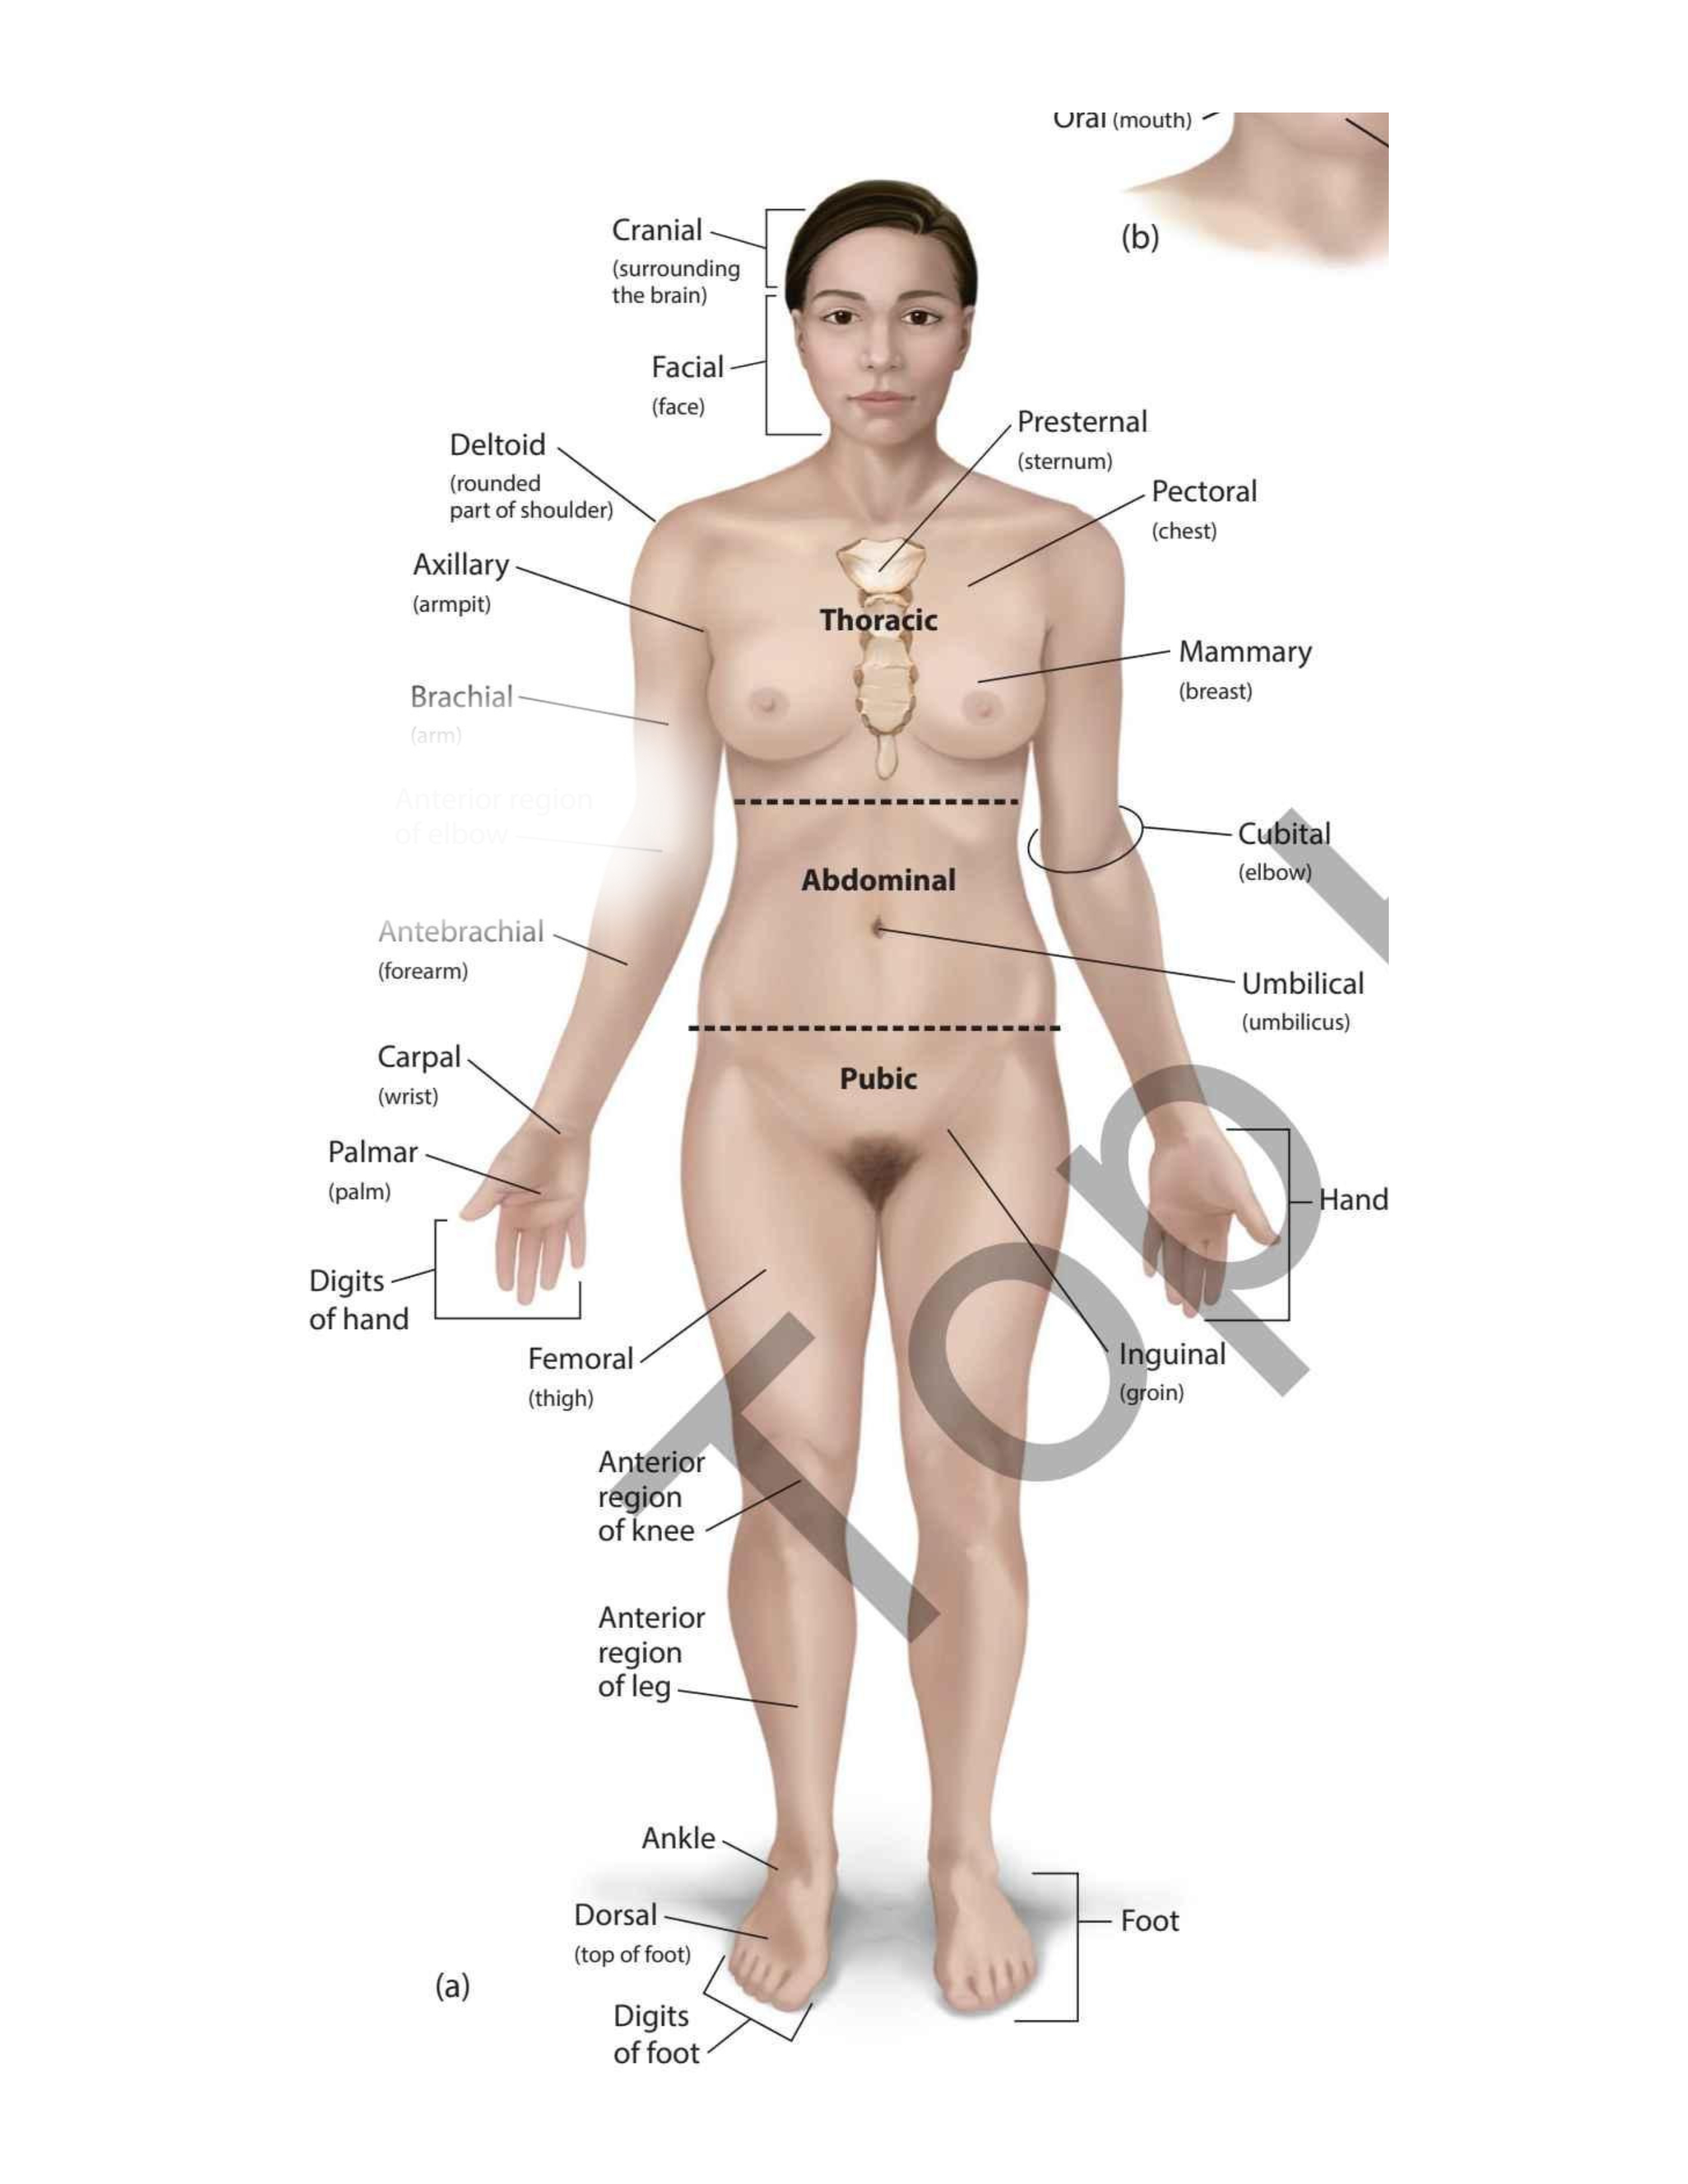

(forehead)

Frontal

(chin)

Mental

(wrist)

Carpal

(thigh)

Femoral

(elbow)

Antecubital

(back elbow)

Olecranal

(back knee)

Popliteal

(heel)

Calcaneal

(shoulder blades)

Scapular

(sole)

Plantar